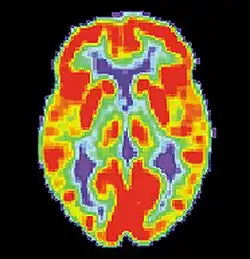

Tomografia emisyjna pojedynczych fotonów, badanie SPECT (od ang. single-photon emission computed tomography) – tomograficzna technika z dziedziny medycyny nuklearnej, która przy użyciu promieniowania gamma umożliwia tworzenie obrazu przestrzennego aktywności biologicznej dowolnego obszaru ciała pacjenta[1].

Badania SPECT znalazły szerokie zastosowanie w neurologii. Stosuje się je do badania przepływu mózgowego krwi, guzów mózgu i rozmieszczenia receptorów (opiatowych, benzodiazepinowych, muskarynowych i dopaminowych). Wykorzystuje się do tego dwa radiofarmaceutyki 99mTc-HMPAO i 99mTc-ECD. Pierwszy stosowany jest do badania zmian zachodzących w dużych i średnich naczyniach mózgowych, a drugi do badania przepływu miąższowego.

Jeżeli znacznik w jakimś miejscu nie gromadzi się lub gromadzi w widocznie mniejszym stopniu, oznacza to niedokrwienie ośrodkowego układu nerwowego. Istnieją dwie metody analizy danych uzyskanych w wyniku tego badania. Analiza jakościowa, która polega na ocenie rozmieszczeniu radiofarmaceutyka w tkance mózgu oraz analiza półilościowa, która polega na ocenie międzypółkulowej lub wewnątrzpółkulowej asymetrii perfuzji.

SPECT umożliwia dostrzeżenie ognisk niedokrwiennych zaraz po zablokowaniu naczynia, w niepełnej martwicy neuronalnej oraz niedokrwienia względnego, co byłoby niemożliwe przy wykorzystaniu innych metod obrazowania medycyny nuklearnej.